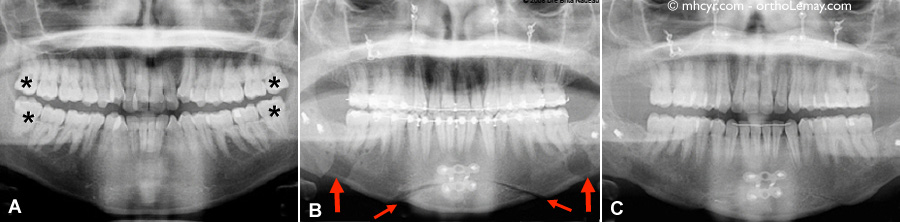

Les radiographies panoramiques pendant le traitement.

Les radiographies panoramiques pendant le traitement. (A) Avant le traitement, on remarque la présence des 4 dents de sagesse indiquées par des astérisques noirs (*). Les dents de sagesse inférieures doivent être enlevées plusieurs mois avant la chirurgie afin de minimiser les chances d’une “mauvaise fracture” lors de l’ostéotomie d’avancement mandibulaire. (B) Après la chirurgie (les dents de sagesse ont été extraites), on remarque les zones de coupe qui sont plus foncées (ostéotomies) dans la région arrière de la mandibule (grosses flèches) et dans le menton (petites flèches). On peut aussi voir plusieurs vis et plaques de fixation posées lors de la chirurgie pour fixer les segments osseux. (C) À la fin du traitement, les zones de coupes se sont minéralisées et ressemblent presque à de l’os normal. Ce processus prend plusieurs mois à se compléter. Les vis et plaques sont habituellement laissées en place si elles ne causent pas de problèmes.